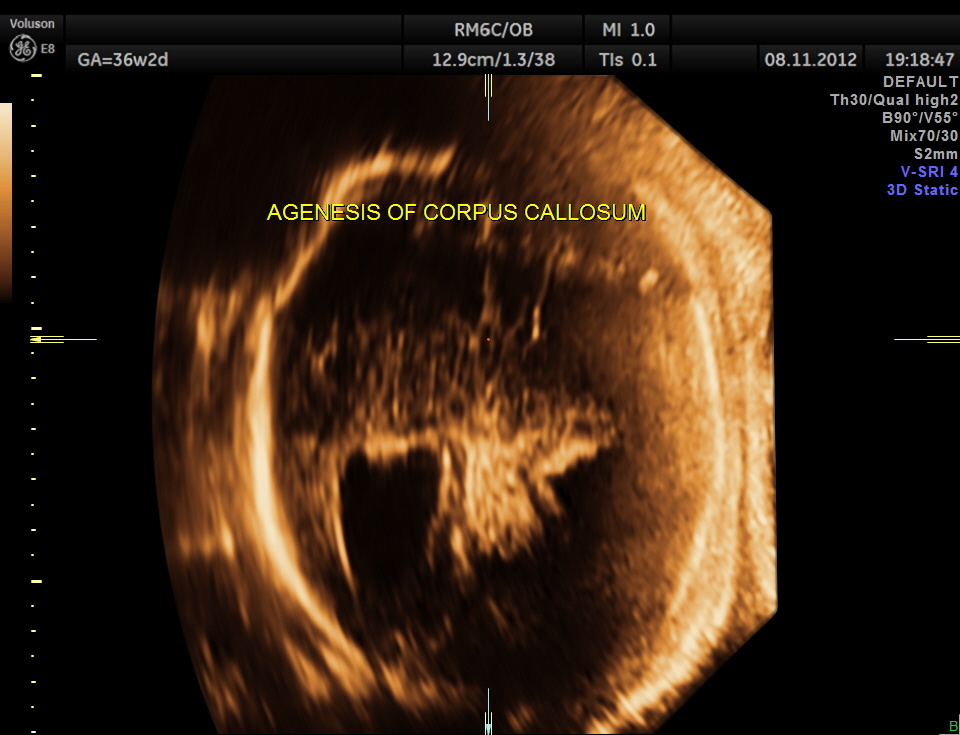

A specific diagnosis of agenesis of the corpus callosum has seldom been made before the third trimester, probably because the corpus callosum is not normally formed until 18 to 20 weeks43. Most authors agree that detection of agenesis of the corpus callosum is difficult prenatally, depending as it does on postnatal sonograms or CT or MR scans. In a series of seven fetuses with agenesis of the corpus callosum, Bertino et al35 reported that only three demonstrated a characteristic midline cyst. They described three findings that might lead one to suspect agenesis of the corpus callosum on routine transverse views:

- disproportionate enlargement of the occipital horn,

The increased separation of the normal-sized bodies and the enlargement of the atria and occipital horns of the lateral ventricle result in a typical ultrasound image. Upward displacement of the third ventricle is a very specific sign36 but presents only in 40% of fetuses.